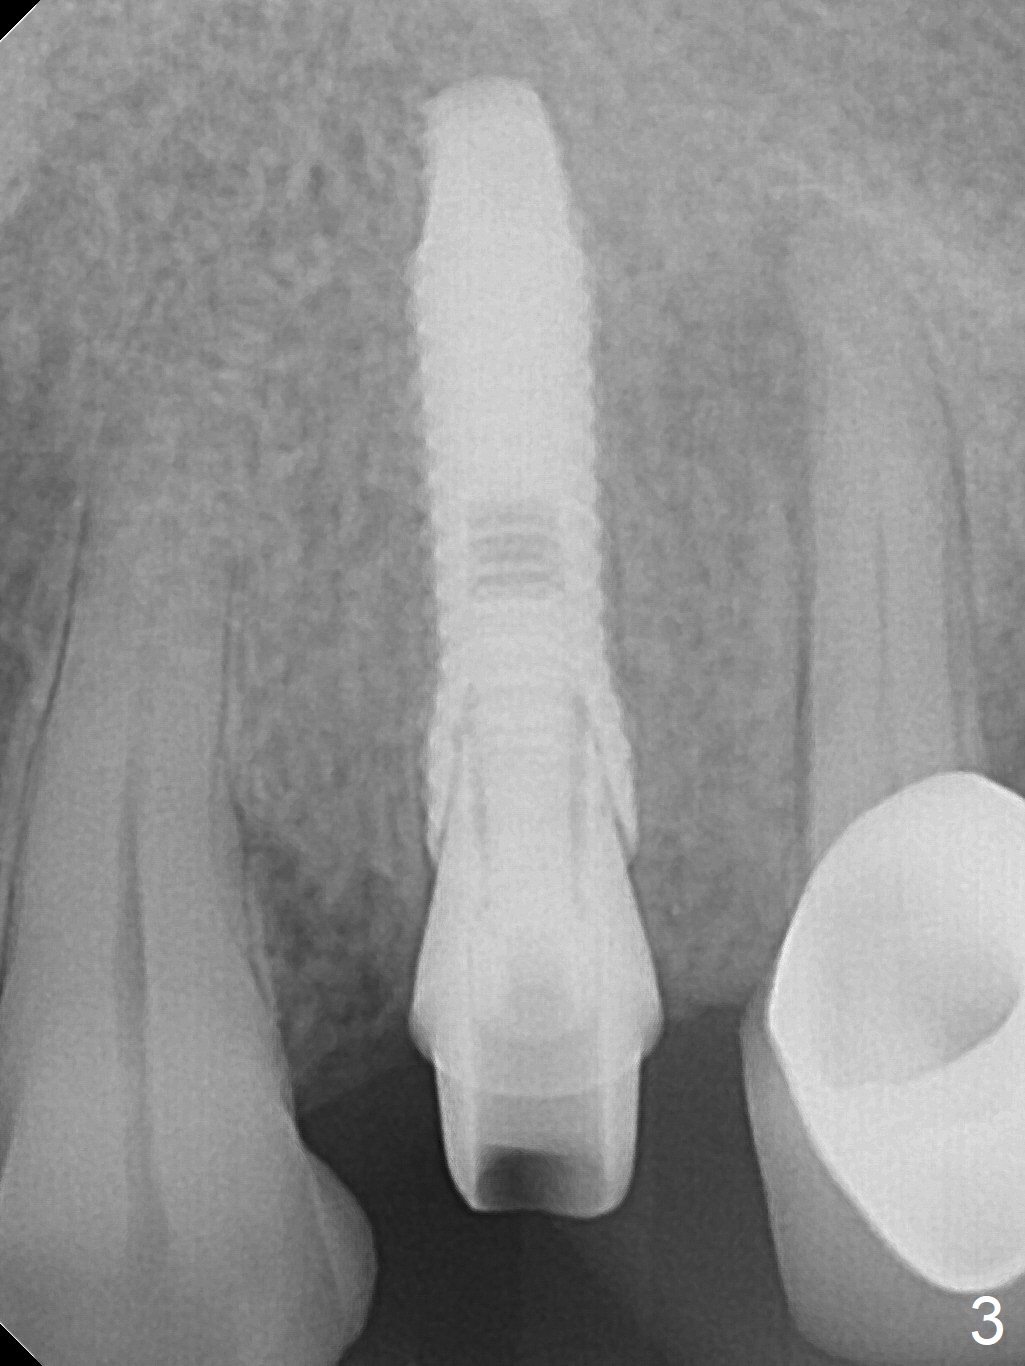

After extraction of the oval-shaped residual roots at #12 (Fig.1), osteotomy is initiated in the palatal socket for 18 mm; since the root of the canine curves distal (Fig.2 red dashed line), the osteotomy cannot afford to move mesial and extend more apical. A 3.8x15 mm implant is placed with > 50 Ncm (Fig.3). With immediate placement of a 4.5x4(3) mm abutment, an immediate provisional is fabricated to close the sockets (Fig.4 P). The provisional has clearance from the RPD clasps (Fig.5). In fact the implant could be longer, as shown by immediately postop panoramic X-ray (Fig.6). The implant seems to be osteointegrated 3 months postop (Fig.7). The tooth #13 is symptomatic with caries (Fig.8 C) 7 months post #12 crown cementation; the #13-15 FPD dislodges. The upper left quadrant is cold and hot sensitive 2.5 months post RCT (Fig.9); although there is mild percussion at #13, pulpal test shows that the tooth #15 has lingering pain. The FPD was recemented temporarily after RCT; it cannot be removed. The implant crown has been loose for several months during the pandemic before he returns 2 years 7 months post cementation. In fact the abutment has been not seated completely (from Fig.3 to 9). The crown/abutment is removed from the mouth; the crown is sectioned and separated from the abutment; the latter is reseated, but incompletely (Fig.10 <). With suspicion of the mesial crestal contact, profile drills 4.6 and 5.5 mm are used without effect. A new (old probably being worn) and longer (easy to turn in the narrow space) abutment is finally seated completely (Fig.11 (no gap)). After occlusal adjustment, abutment level impression is taken for a new crown.